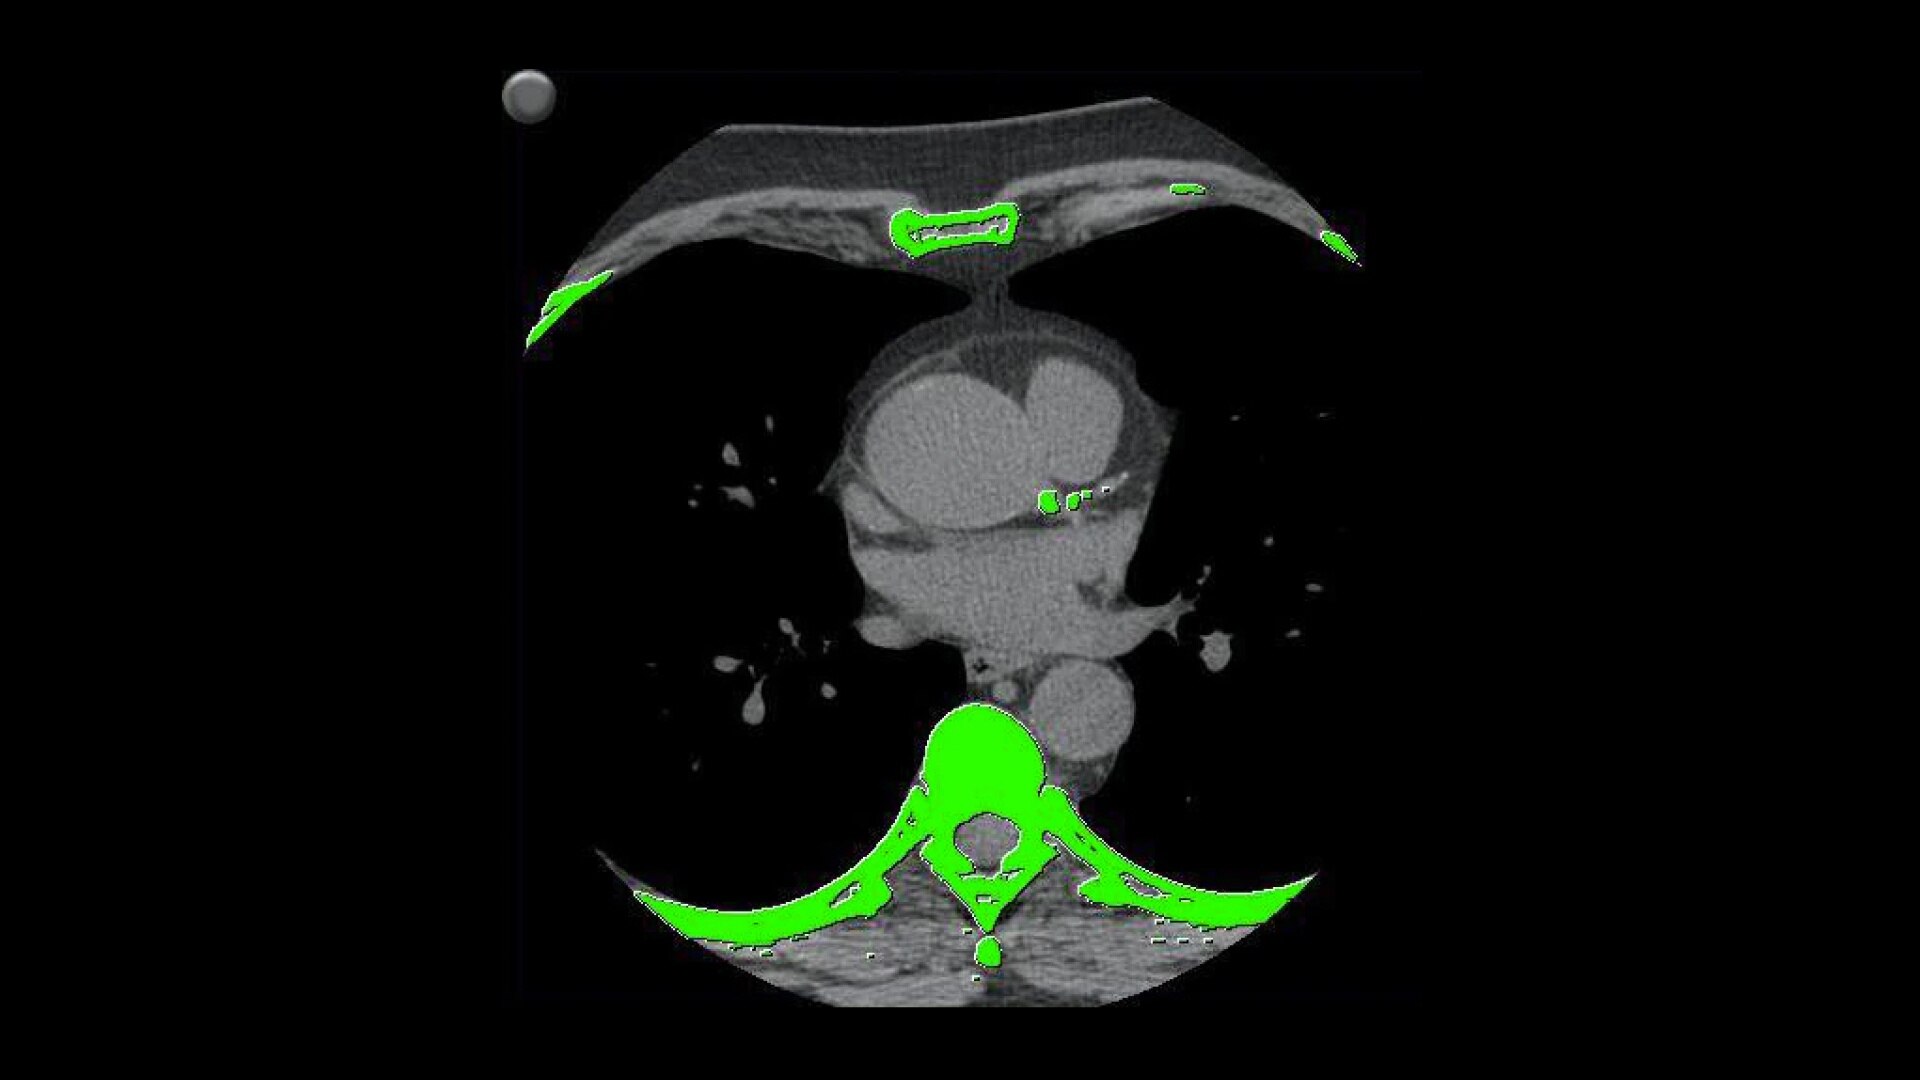

• Automatically detects calcium and highlights it in green

• AJ 130 scoring method uses conventional Agatston/Janowitz technique with a threshold of 130

• HU which is adjusted to the appropriate image slice thickness

• Volume scoring calculates volumes (mm3) of calcified plaque above the 130 HU threshold

• Mass scoring calculates mass (mg) of calcified plaque above the 130 HU threshold